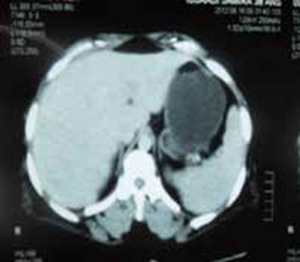

La tomodensitométrie abdominale avec opacification confirmait cette cholécystite avec un foie hétérogène, siège de multiples microlésions arrondies hypodenses, rehaussées légèrement après injection de produit de contraste (Figures 3, 4).